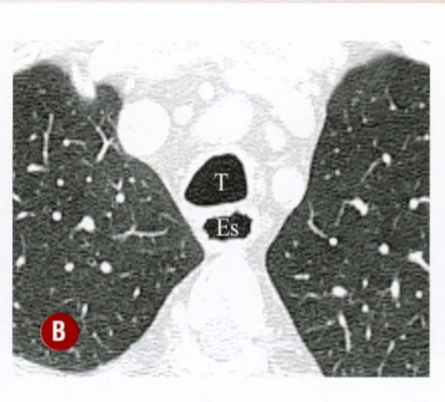

Esse tórax se encontra na inspiração ou na expiração ? Porque?

Inspiratório, mostrando convexidade posterior da parede traqueal

Final da inspiração , mostra o diâmetro AP da traquéia e convexidade anterior da parede posterior